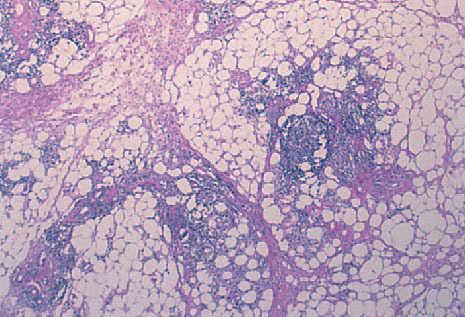

Se realizó estudio histológico de las lesiones de brazo y cara. La lesión del brazo mostró, bajo una epidermis de aspecto normal, un infiltrado linfohistiocitario en septos y lóbulos, con extensión a dermis profunda. En los lóbulos se formaban acumulaciones de linfocitos que simulaban centros foliculares. También se observaba discreta necrosis hialina de la grasa y depósito de mucina (fig. 3). La biopsia facial presentó afectación típica de LED, con hiperqueratosis folicular, degeneración hidrópica de la basal y un infiltrado linfohistiocitario parcheado en dermis de predominio perivascular y perianexial.

Fig. 3.—Infiltrado linfohistiocitario en septos y lóbulos con formación de centros foliculares en los lóbulos y depósito discreto de mucina. (Hematoxilina-eosina, ×40.)